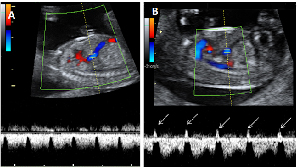

La ecografía en tres dimensiones muestra un feto de 13 semanas de gestación con el cordón umbilical alrededor del cuello. En la imagen rotatoria se puede observar la situación del cordón, que sube por el tórax y que seguramente puede causar complicaciones en el embarazo.